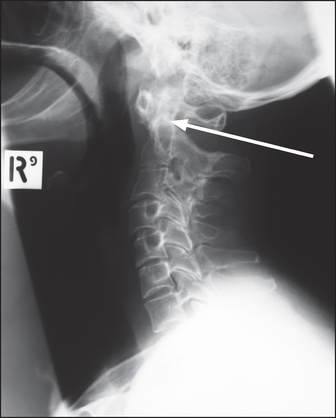

Figure 26.3 Rheumatoid arthritis Lateral X-ray of the cervical spine showing anterior subluxation of the anterior arch of the dens of the axis (C2, arrow).